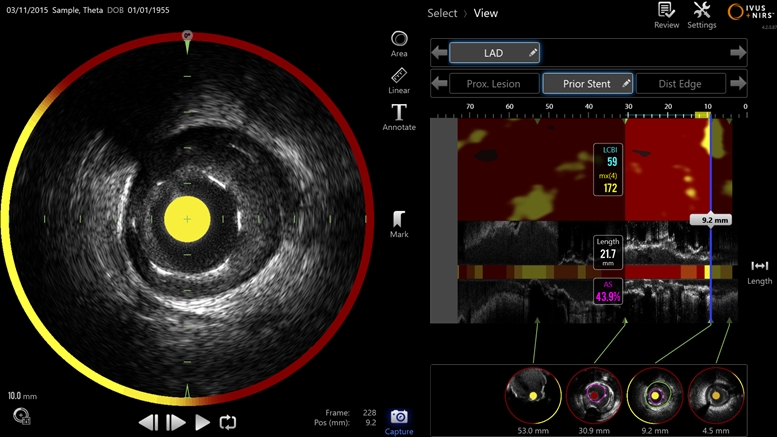

Ultrasonic intravascular imaging is used to determine the degree to which arteries are blocked by plaques, but the specific chemical nature of those plaques is thought to be critical in deciding whether or not the blockage will lead to a serious cardiac event such as a heart attack. Infraredx's dual-mode technology combines ultrasound with near-infrared spectroscopy to detail both the blockage and its chemical make-up. Image: Infraredx.

The catheter-delivered imaging tool is said to exploit the dual modality approach by both mapping the shape of blocked blood vessels and identifying the chemical composition of the plaque creating the blockage. Japan's Pharmaceuticals and Medical Devices Agency (PMDA) approved the technology in August 2017.

The Makoto system features a "Dualpro" imaging catheter equipped with an extended ultrasound bandwidth. "By emitting and carefully processing a broad band of frequencies, the Dualpro IVUS provides best-in-class image resolution without compromising depth of field," states Infraredx, advantages said to translate to crisper arterial imagery.

That information is combined with near-infrared spectroscopic (NIRS) data and translated into a color-coded map to identify lipid core plaque (LCP) features. That information can help cardiologists distinguish between stable and dangerous plaques inside a patient's arteries.